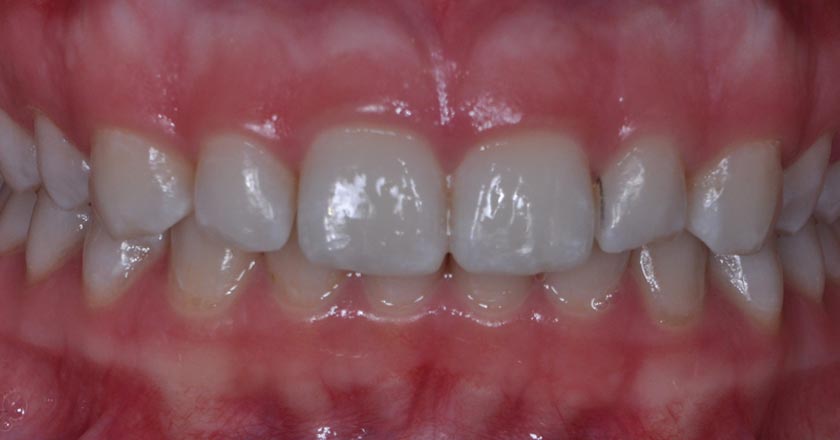

Gummy Smile - Before And After

Gummy smile correction – before treatment 1

Gummy smile correction – after treatment 1